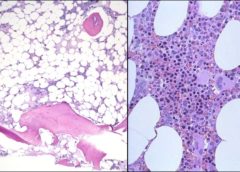

Anche i batteri del tessuto mammario possono influire sull’insorgenza del tumore del seno. A suggerire la correlazione è uno studio collaborativo tra la Fondazione Policlinico Universitario A. Gemelli IRCCS, Università Cattolica e l’Università della Tuscia, pubblicato su Scientific Reports, coordinato da Riccardo Masetti, Direttore…